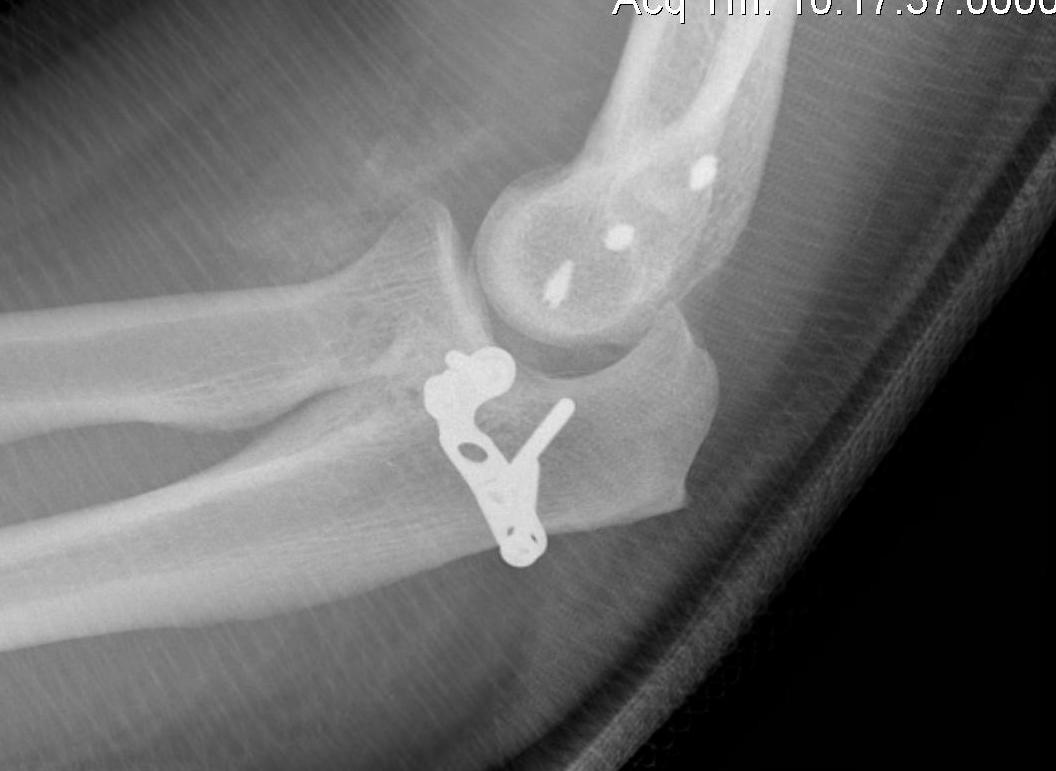

Fixation

AO surgery reference coronoid fixation

Lasso Suture bone + capsule - pass through drill holes in ulna and tie over button

Screw fixation - AP or PA

Buttress plate - medial approach to anteromedial fragment

Unrepairable - reconstruct with radial head / iliac crest / allograft

Approach through radial head, suture fixation and repair over button

Medial approach and screw fixation

Medial approach and buttress plate with LCL repair

Universal posterior approach with radial head replacement and medial approach with medial buttress plate

Medial approach and buttress plate for basilar fracture with olecranon fracture